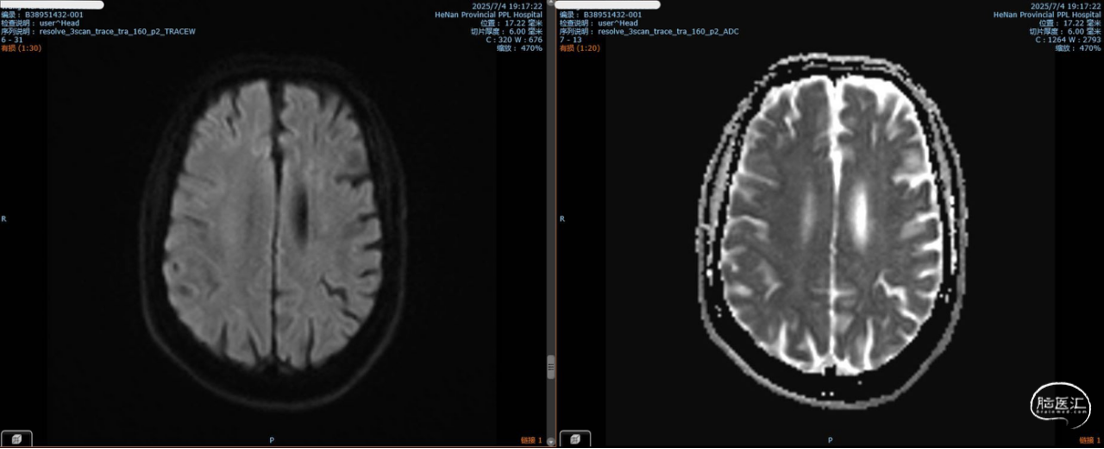

术后第七天,头部MRI提示左侧额顶叶急性脑梗死。

2025-7患者再次入院拟手术治疗,术前查体右侧肢体肌力4级,2025-7-7完成EDAS手术,术后第三天患者出现咳嗽咳痰、发热,次日患者病情进展,精神差、进食差、频繁呕吐和腹泻,结合头胸部CT及实验室检查明确患者双肺重度肺炎、肺水肿、胸腔积液、心衰、酮症酸中毒;予以转入CCU专科治疗,治疗期间患者出现口角歪斜、言语不清、右侧肢体肌力降低至4-级,头部MRI提示左侧额顶叶急性脑梗死;术后第七天内环境及心肺功能稳定后转回普通病房;术后第十天患者肌力和言语不清开始改善,至术后第十四天出院患者口角歪斜、言语不清明显改善,右侧肢体肌力改善至5-级。